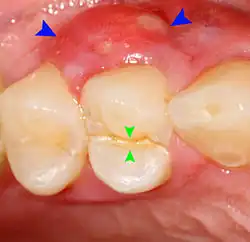

Pericoronitis

Pericoronitis is inflammation of the soft tissues surrounding the crown of a partially erupted tooth.[25] The lower wisdom tooth is the last tooth to erupt into the mouth, and is, therefore, more frequently impacted, or stuck, against the other teeth. This leaves the tooth partially erupted into the mouth, and there frequently is a flap of gum (an operculum), overlying the tooth. Bacteria and food debris accumulate beneath the operculum, which is an area that is difficult to keep clean because it is hidden and far back in the mouth. The opposing upper wisdom tooth also tends to have sharp cusps and over-erupt because it has no opposing tooth to bite into, and instead traumatizes the operculum further. Periodontitis and dental caries may develop on either the third or second molars, and chronic inflammation develops in the soft tissues. Chronic pericoronitis may not cause any pain, but an acute pericoronitis episode is often associated with pericoronal abscess formation. Typical signs and symptoms of a pericoronal abscess include severe, throbbing pain, which may radiate to adjacent areas in the head and neck,[21][26]: 122 redness, swelling and tenderness of the gum over the tooth.[27]: 220–222 There may be trismus (difficulty opening the mouth),[27]: 220–222 facial swelling, and rubor (flushing) of the cheek that overlies the angle of the jaw.[21][26]: 122 Persons typically develop pericoronitis in their late teens and early 20s,[28]: 6 as this is the age that the wisdom teeth are erupting. Treatment for acute conditions includes cleaning the area under the operculum with an antiseptic solution, painkillers, and antibiotics if indicated. After the acute episode has been controlled, the definitive treatment is usually by tooth extraction or, less commonly, the soft tissue is removed (operculectomy). If the tooth is kept, good oral hygiene is required to keep the area free of debris to prevent recurrence of the infection.[21]: 440–441